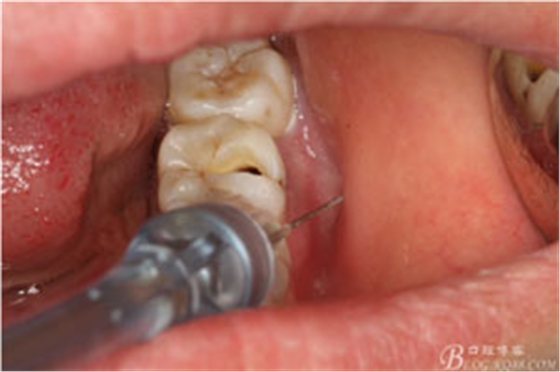

圖3.取出棉球口內(nèi)發(fā)現(xiàn)37合面有開(kāi)髓孔,探針出血,頰側(cè)牙齦紅腫

圖4.行下頜無(wú)痛阻滯麻醉

圖5.加局部浸潤(rùn)麻醉